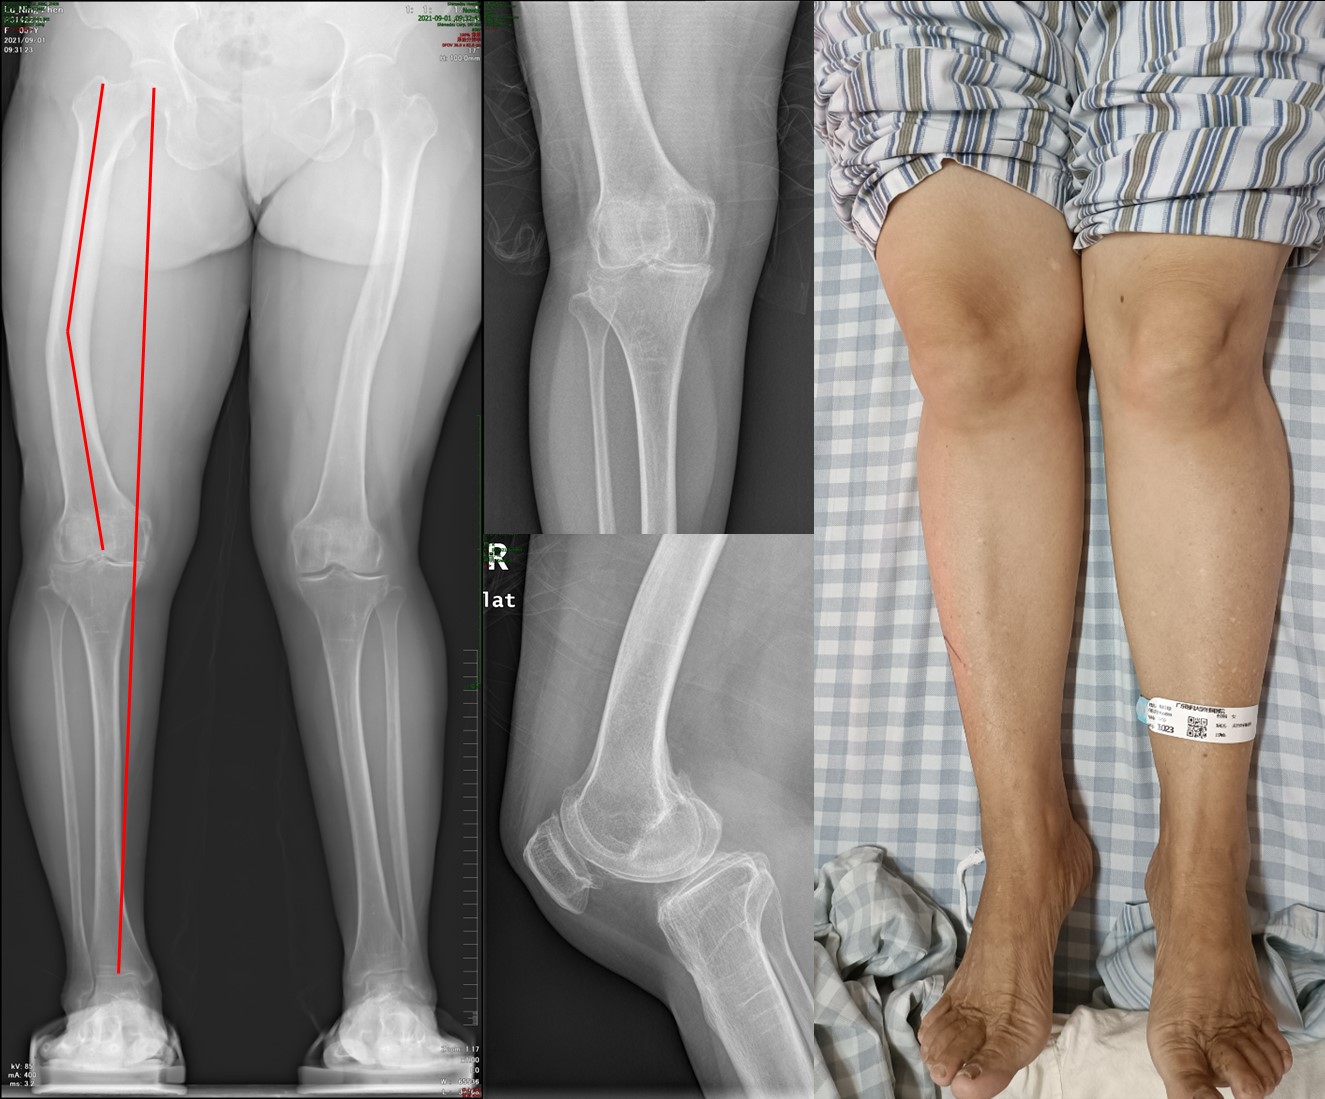

术中,通过3D打印导板的定位辅助下,股骨远端截骨并未受到关节外畸形的丝毫影响,截骨和假体的安装均一步到位(图3)。在麻醉团队副主任医师李大桁和手术室护理团队的通力协作下,手术时间甚至比常规手术用时更短,仅50分钟便完成了假体的安放。在病区护士长郑越瑜和主管护师庞少波悉心的康复训练指导下,术后第二天患者即下地负重,复查双下肢x线提示股骨侧假体力线恢复近乎完美,而原有畸形今后无需再接受额外的手术矫正(图4)。对于这一手术效果,陆阿姨表示十分满意,由衷感谢钟环主任团队能够站在患者角度为其实施最佳的手术方案。

图4良好的术后关节功能和假体对线